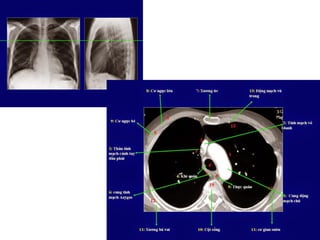

Giải phẩu CT ngực – các mạch máu

lớn.

SVC: tĩnh mạch chủ trên.

Aortic arch: cung đm chủ

Pulmonary artery: đm phổi

Main sterm bronchus: phế quản gốc

63